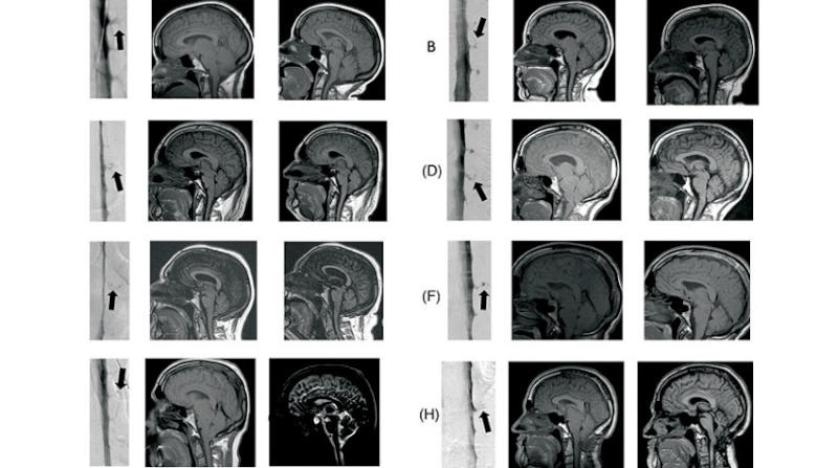

وأحد أسباب المرض، هو حدوث تسرب للسائل النخاعي، الذي يدور في الدماغ والحبل الشوكي وحولهما، للمساعدة في الحماية من الإصابة، فعندما يتسرب هذا السائل إلى الجسم، يمكن أن يحدث «ترهل الدماغ»، ما يسبب أعراض الخرف.

وعندما يتسرب السائل من خلال تمزق في الغشاء المحيط، فإنه يكون مرئياً في التصوير المقطعي المحوسب للنخاع بمساعدة وسيط التباين، وبالتالي يمكن علاج هذه الحالة، ولكن الجديد الذي اكتشفه الفريق البحثي، وتم نشره الثلاثاء في دورية «ترانسليشن ريسيرش & كلينكال إنترفينشين»، أن هناك سبباً إضافياً لتسرب السائل الدماغي النخاعي، وهو «ناسور السائل النخاعي الوريدي»، وفي هذه الحالات، يتسرب السائل إلى الوريد، ما يجعل من الصعب رؤيته في التصوير المقطعي للنخاع الروتيني، وللكشف عن هذه التسريبات، يجب على الفنيين استخدام الأشعة المقطعية المتخصصة ومراقبة وسيط التباين أثناء حركته وأثناء تدفقه عبر السائل النخاعي.

وفي هذه الدراسة، استخدم الباحثون تقنية التصوير على 21 مريضاً يعانون من ترهل الدماغ وأعراض «الخرف الجبهي الصدغي»، واكتشفوا «ناسور السائل النخاعي الوريدي»، في تسعة من هؤلاء المرضى، وتم إغلاق التسرب جراحياً في جميع المرضى التسعة، وهو ما ساعد في علاج ترهل الدماغ والأعراض المصاحبة للخرف.